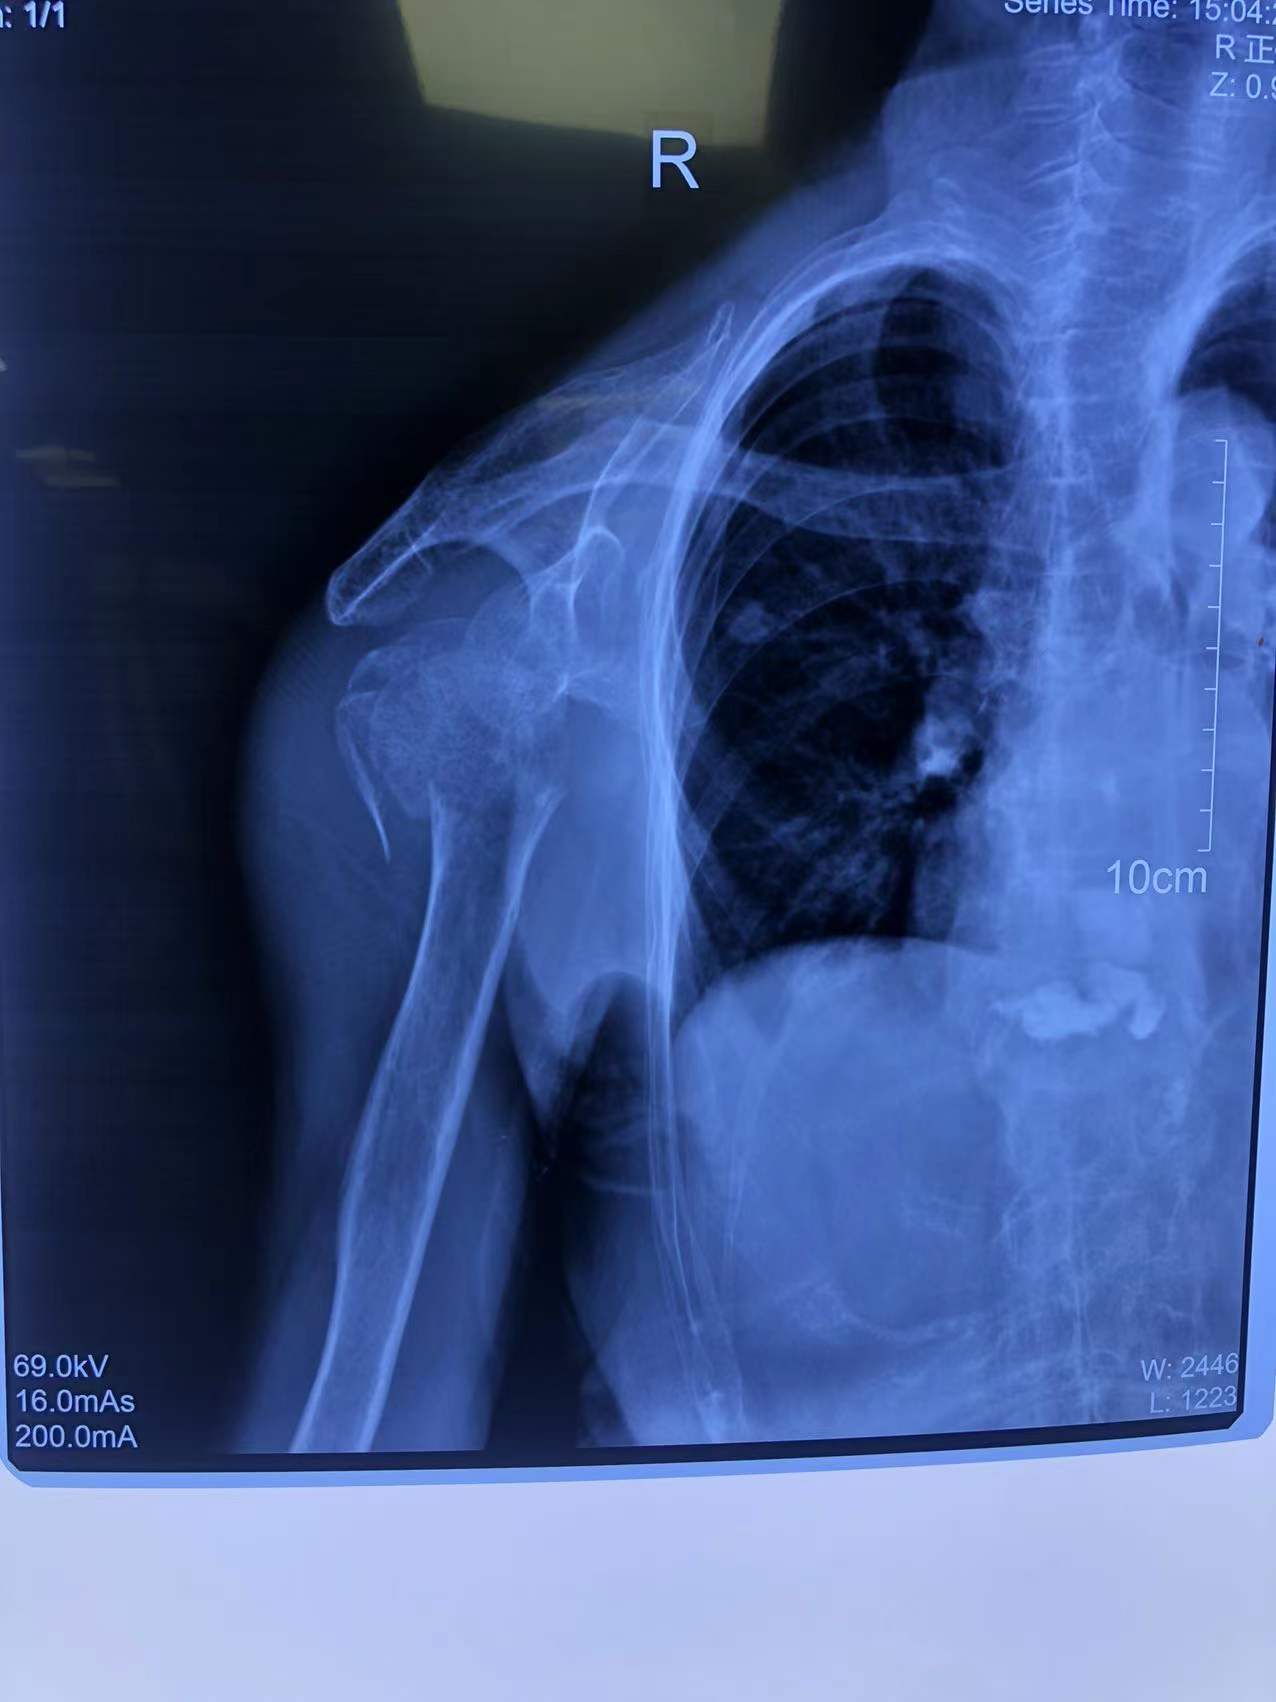

80歲的李老太(化名)走路時(shí)不慎摔了一跤,雖然感覺(jué)右肩膀和上臂疼痛劇烈,但她想著休息休息就沒(méi)事兒了,便沒(méi)有第一時(shí)間前往醫(yī)院看診。然而,接下來(lái)的幾天,疼痛不但沒(méi)有好轉(zhuǎn),反而愈演愈烈,這才被家人著急忙慌送到了石化醫(yī)院。行右肩X線檢查,原來(lái),李老太右肱骨近端粉碎性骨折,隨后收住骨科。

李老太是粉碎性骨折,情況較為嚴(yán)重,為恢復(fù)肩關(guān)節(jié)功能,石化醫(yī)院骨科副主任張明龍帶領(lǐng)團(tuán)隊(duì)充分評(píng)估病情,與病人和家屬協(xié)商后,決定實(shí)施人工肱骨頭置換術(shù),在右肩安裝一個(gè)“人工肩關(guān)節(jié)”。